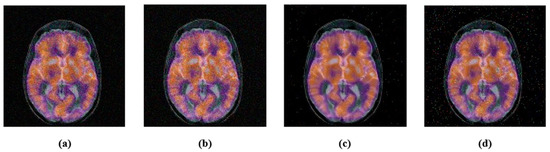

- Johnson, K.A.; Becker, J.A. The Whole Brain Atlas. Available online: http://www.med.harvard.edu/AANLIB/home.html (accessed on 19 April 2022).